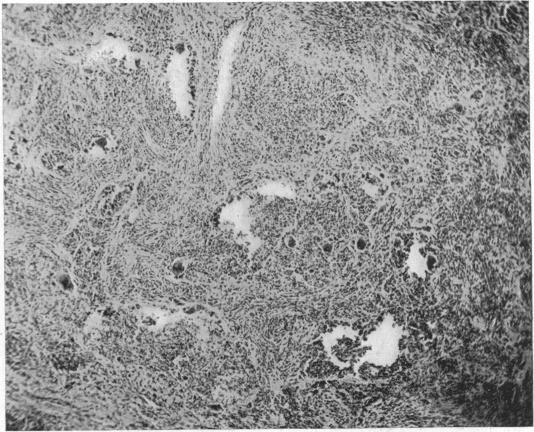

BENIGN XANTHIC EXTRAPERIOSTEAL TUMOR OF THE EXTREMITIES CONTAINING FOREIGN BODY GIANT CELLS.

Ann Surg. 1919 Nov;70(5):574-81. doi: 10.1097/00000658-191911000-00011.